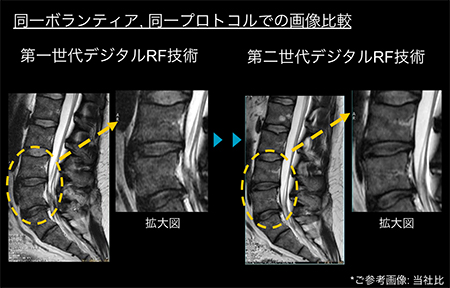

高いSNRによる高分解能イメージング

・第二世代のデジタルRF技術:「TDI(Total Digital Imaging) RFテクノロジー」により,最大59%*3のSNRが向上します。

*3 自社アナログMRとの比較